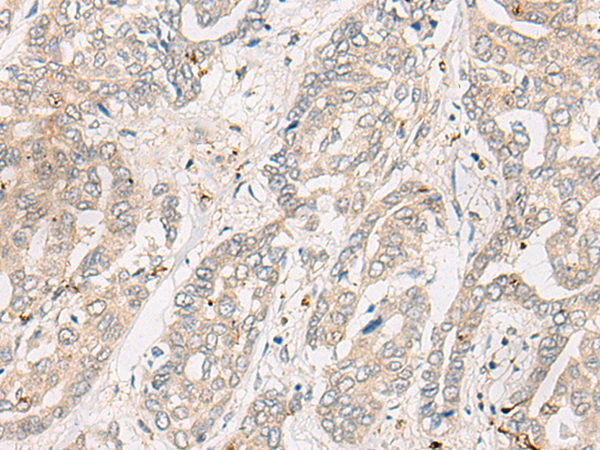

分类: 科研抗体货号: P02597别名: dJ94G16.1应用: IHC反应种属: Human